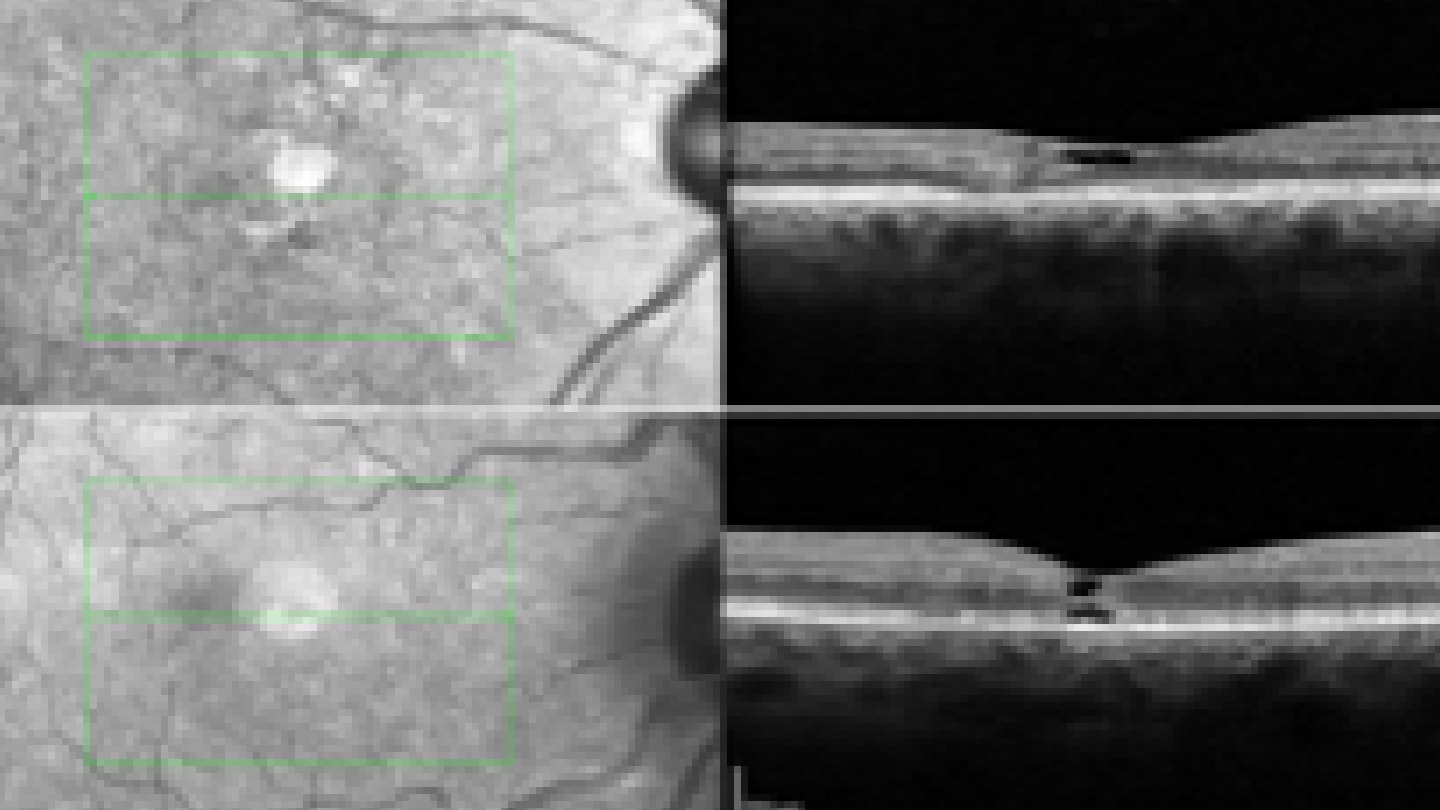

In my practice, spectral-domain optical coherence tomography (SD-OCT) serves as the cornerstone diagnostic tool for MacTel. Whether performed before referral or as my first confirmatory step, SD-OCT reveals the disease’s most characteristic early finding: cavitation within the ellipsoid zone (EZ) (Figure 1) (6, 7). This photoreceptor integrity loss, typically temporal to the fovea, manifests as a spectrum ranging from subtle disruption in early disease to pronounced cavitations in advanced cases.

OCT features of MacTel. (A) Focal ellipsoid zone (EZ) discontinuity with outer retinal loss and inner retinal disorganization, sparing foveal center. (B) EZ discontinuity with low-reflective spaces in outer and inner retina, plus hyperreflective external limiting membrane. Reproduced from Chew et al. 2023;3(2):100261.